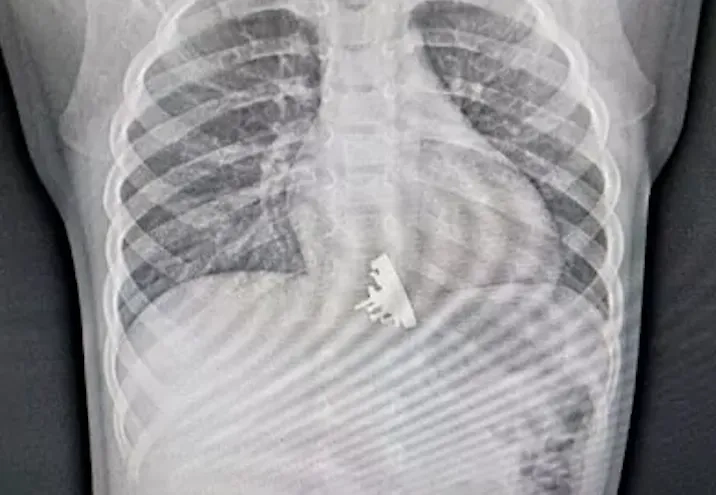

В Иркутске в Ивано-Матренинскую детскую клиническую больницу попала двухлетняя девочка. Осмотрев её рентгеновские снимки, врачи были шокированы. В пищеводе ребёнка застрял металлический игрушечный крейсер "Аврора". Оказалось, что малышка проглотила часть конструктора во время игры.

"Мы сразу заметили, что эта вещь имеет довольно острые выступающие части. Они цеплялись за стены пищевода девочки и царапали его", — рассказал врач отделения эндоскопии ДКБ Илья Пикало в беседе с kp.ru.

Изъять игрушку оказалось сложнее, чем обычные находки в виде монет и прочих гладких предметов, однако специалисты справились и после "абордажа" оставили девочку под наблюдением медперсонала.